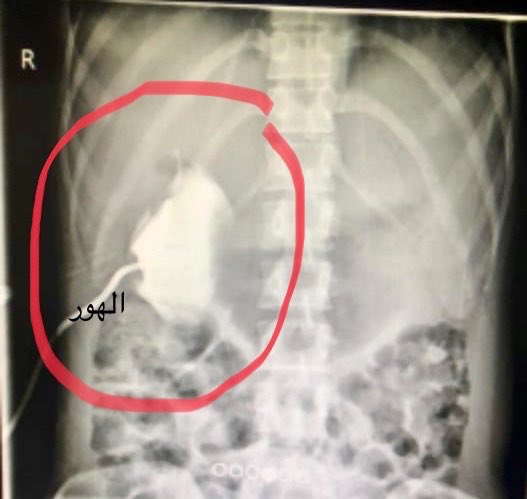

الحالة؛ تكيس القنوات المراريه وهو عيب خلقي و قد يتحول الى ورم خبيث في اي وقت وهي تعلم جيداً هذا الخطر ان لم تكن أصلاً تعاني منه..

كيس القنوات المراريه👇في حجم اكبر من البرتقالة

وبعدها حصل لديها التهاب شديد في القنوات المراريه مما استدعى تدخل موقت وسريع وهو وضع أنبوب لشفط الصفراء كمخرج موقت و تقوم هي باخلاء الكيس بصوره يوميه من٥٠٠ملم من العصارة الصفراويه.